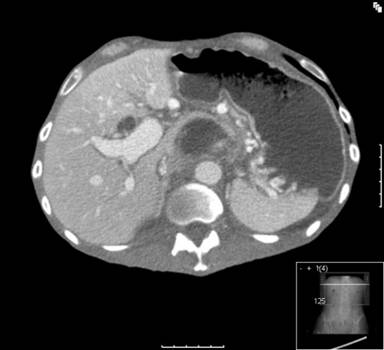

A contrast enhanced pancreatic protocol CT from November 2008 demonstrated ductal irregularities and pancreatic parenchymal calcification associated with a possible superior mesenteric vein thrombosis. He was readmitted in March 2009 for an exacerbation of abdominal pain and weight loss. He was treated with pancreatic rest, nutritional support, and analgesia. His serum biochemistry demonstrated an elevated CA 19-9 (1,000 IU/mL; reference range: 0-34 IU/mL) and CEA (17 µg/L; reference range: 0-4 µg/L) and an urgent abdominal CT scan demonstrated a 3.5x5.0 cm solid/cystic mass associated with the head of pancreas (Figure 1). The portal vein appeared severely attenuated at its origin for approximately 2 cm but remained patent. The findings were suggestive of malignant change in a background of chronic pancreatitis. His serum IgG4 levels were normal, and he subsequently underwent an EUS guided biopsy of the mass in the head of pancreas.

Figure 1. CT scan showing pseudotumoral cystic lesion in head of pancreas. |